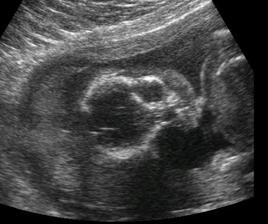

Testy + utz + bříško ♥